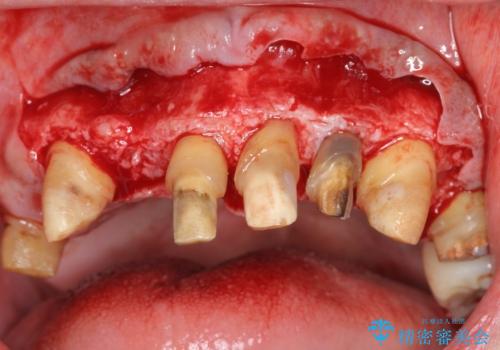

セラミック治療を行う前に歯周病の問題を解決すべく歯周外科を行い歯周ポケットを除去し整備したのちセラミックブリッジ・クラウンの製作を行います。

歯周外科を行ったことで非常に安定した歯周環境となり、引き締まった歯ぐきとなりました。

- 外科手術のため、術後に出血、痛みや腫れ、違和感を伴います

- 外科手術のため、術後に痛みや腫れ、違和感を伴います